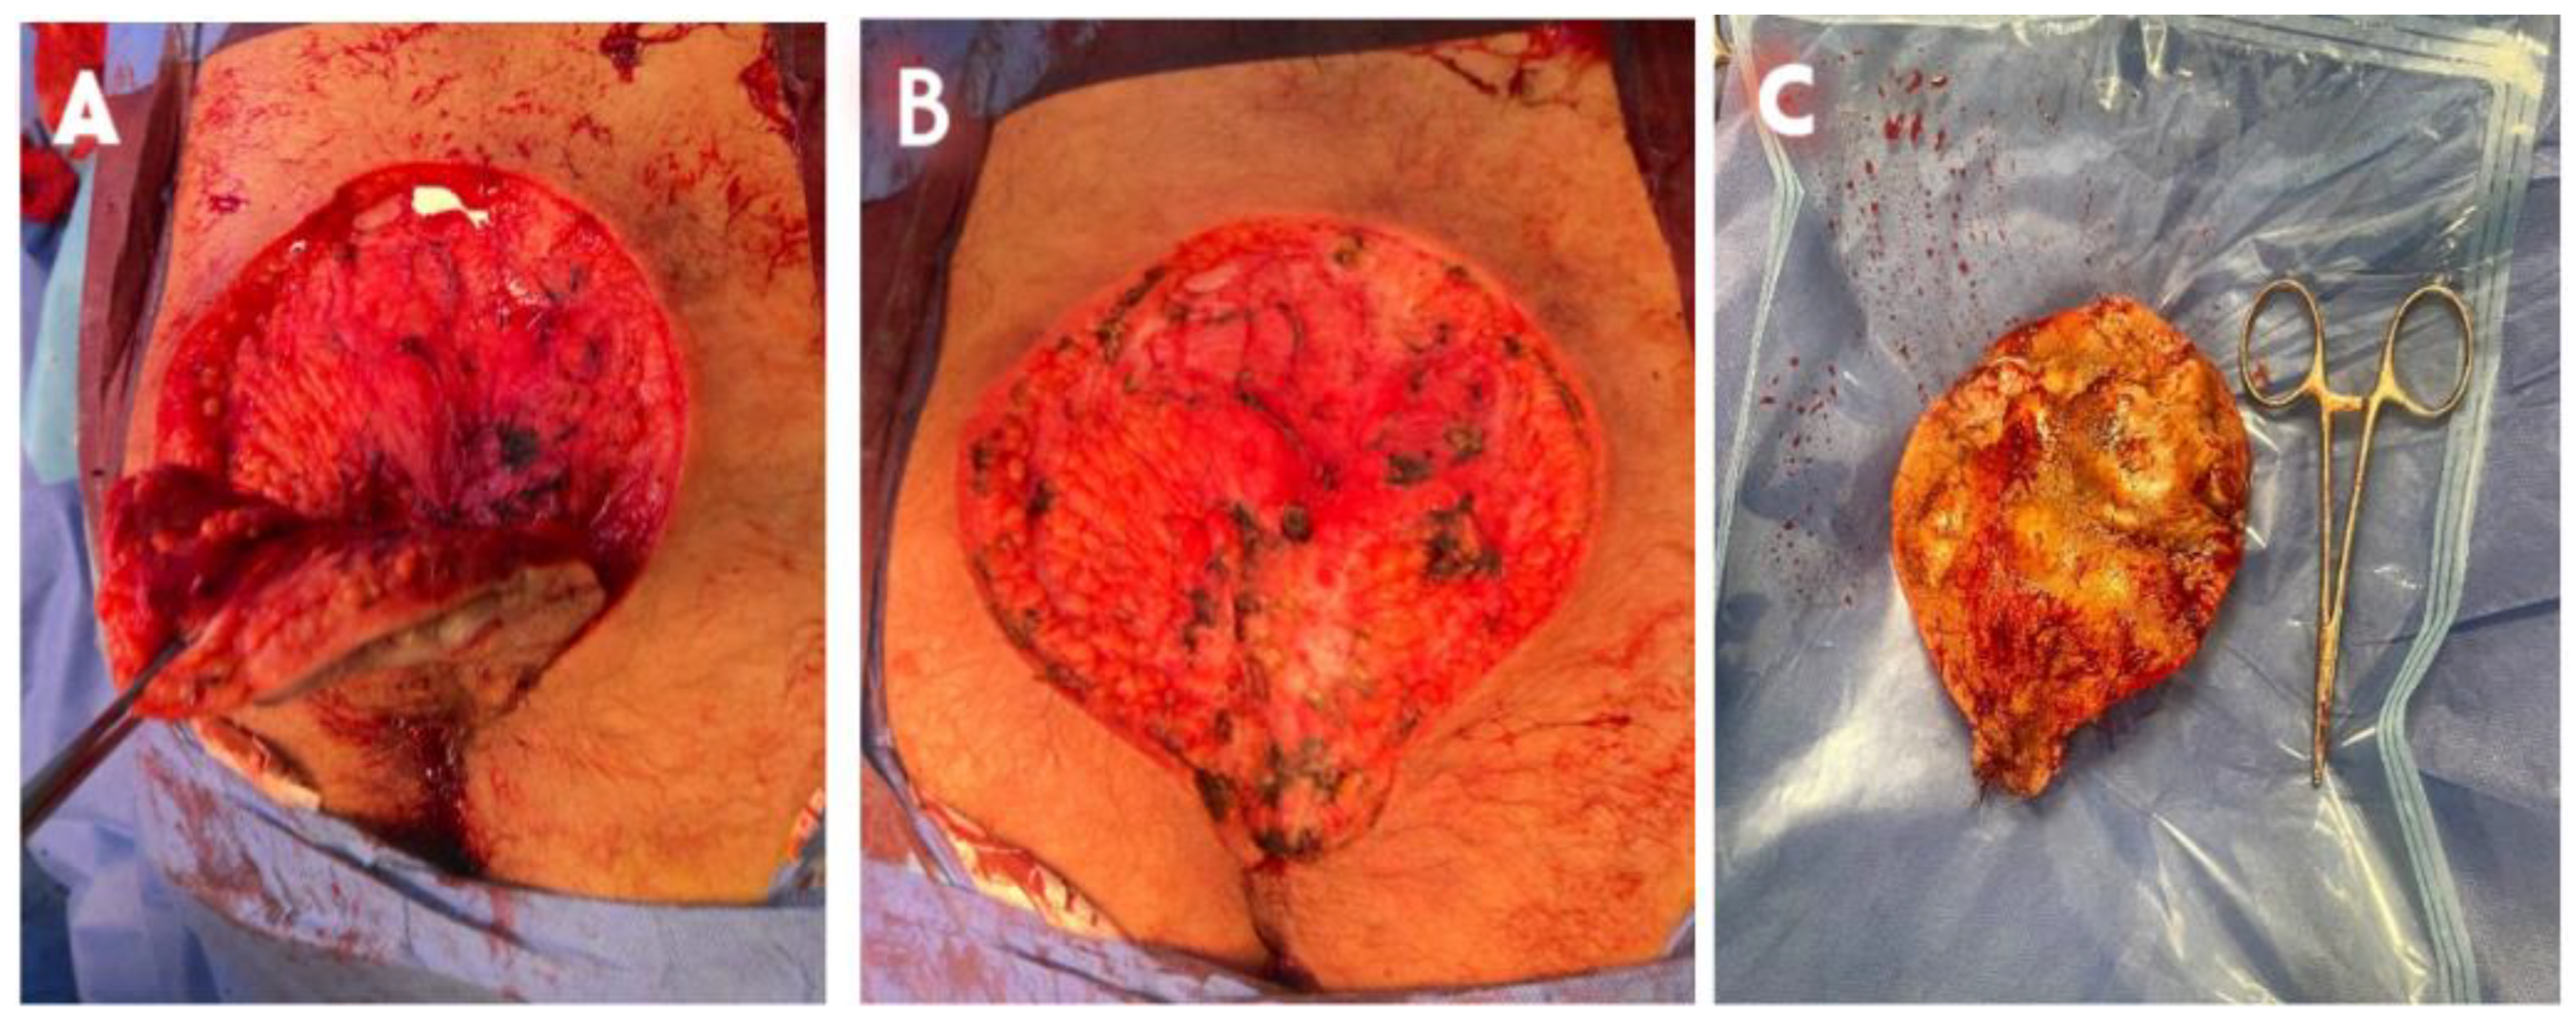

A 34 year old North-African military male, smoker with no past medical or surgery history. With normal BMI of 23. He presented to day-consultation clinic with a good general status, no fever, no jaundice. As the patient reports, the first symptoms appeared 01 year before, through the apparition of lumbar nodule with no other lesion in the arm pits, groin or perineum. The nodule were painful, expanding in volume and number turning to fistulous abscesses over time with purulent discharge causing social disconfort (Figure 1 and Figure 2). Prior to consultation with us, the patient took oral antibiobiotics and some topic antiseptics. The evolution of the lesions motivated a consultation. A clinical evaluation revealed skin ulcers, hyperpigmentation, hardened thick skin folds with orifices discharging pus in the lumbosacral region. Serologic testing for human immunodeficiency virus (HIV), syphilis, chronic infection with hepatitis viruses B and V, as well as chlamydia trachomatis were negative. A computer tomography (CT) imaging concluded with highlighting a polylobed collection associated with multiple fistulous tracts in the subcutaneous soft tissues of the sacrococcygeal region with liquid content showing significant hypersignal on T2 and with a thick wall enhanced after gadolinium injection measuring 20X95X130 mm (Figure 3). There was also soft tissue edema infiltration around the lesion. After the preanesthetic labtest, surgical treatment began. He was placed in ventral decubitus with rachianesthesia. We proceeded with extensive excision of the lesion until presacral fascia in deep with thin (05 mm) normal tissue margin (Figure 4). After careful hemostasis, a sterile dressing was made. The patient was discharged with change of the dressing every 02 days and seen for routine follow-up. Following the procedure, the patient’s recovery was monitored closely, with particular attention to wound healing and any signs of infection. The surgical specimen revealed in pathology lab suppurative hidradenitis with sinus tracts opening with a brisk surrounding inflammatory infiltrate within the dermis (Figure 5). The patient experienced significant improvement in symptoms, and follow-up visits confirmed the effective resolution of the lesion with no immediate recurrence (Figure 6).

Figure 4. (A) Perioperative surgical view of the excision. (B) Large excision down to the fascia. (C) Surgical specimen.